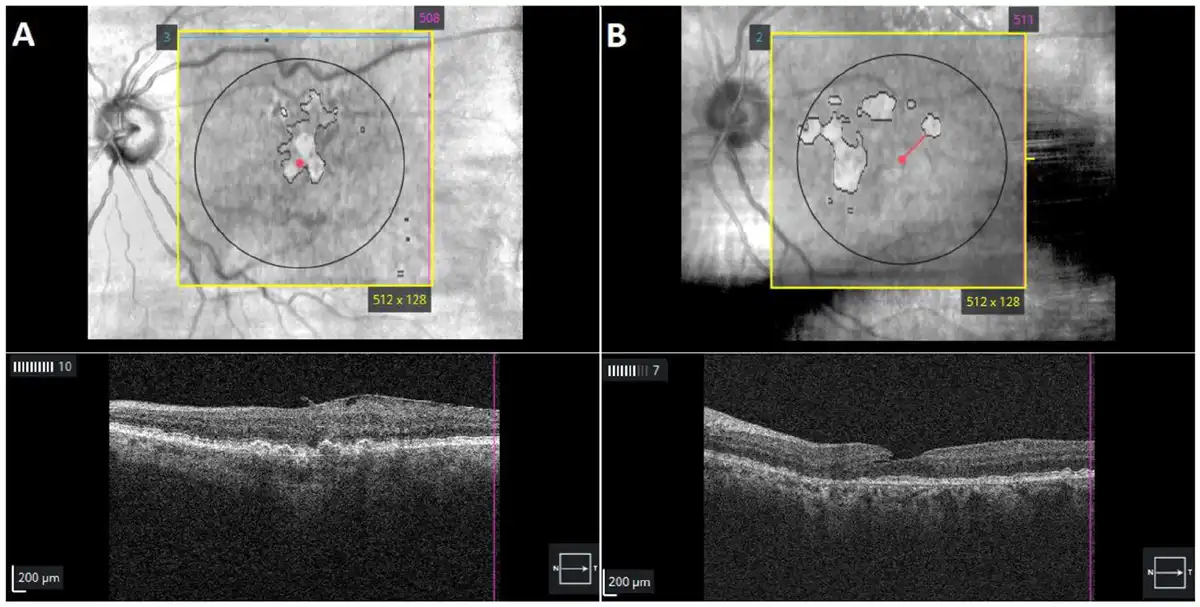

Eyes meeting the inclusion criteria were analyzed using Advanced RPE Analysis software (Zeiss) (Figure 1) to detect the prevalence of undiagnosed GA lesions on the index date. The central subfield thickness (CST), the sub-RPE illumination area within 5.0 mm of the fovea, and the distance of the nearest lesion edge from the fovea (foveal distance) were collected for each eye. As in previous studies, a sub-RPE illumination value of 0.4 mm2 or greater was used as the threshold to identify atrophic lesions. Eyes flagged as having a sub-RPE illumination value of 0.4 mm2 or greater were reviewed by 2 graders (A.S., C.M.) to determine the stage of atrophy, if any, that was present. Staging was according to the Classification of Atrophy Meetings criteria and included incomplete outer retinal atrophy (iORA), complete outer retinal atrophy (cORA), incomplete retinal RPE and outer retinal atrophy (iRORA), and complete RPE and outer retinal atrophy (cRORA). There was 76% agreement between the 2 graders; conflicting grades were resolved through consensus. If lesions were inappropriately shaded by the algorithm, reshading was performed. Only eyes with iRORA and cRORA were considered to have a GA lesion.

Figure 1

Optical coherence tomography of automated subretinal pigment epithelium illumination showing outlines of (A) a fovea-involving lesion with geographic atrophy (GA) and (B) an extrafoveal GA lesion in patients diagnosed with intermediate age-related macular degeneration.